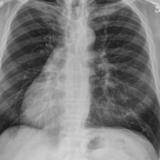

Hypoplastic right lung